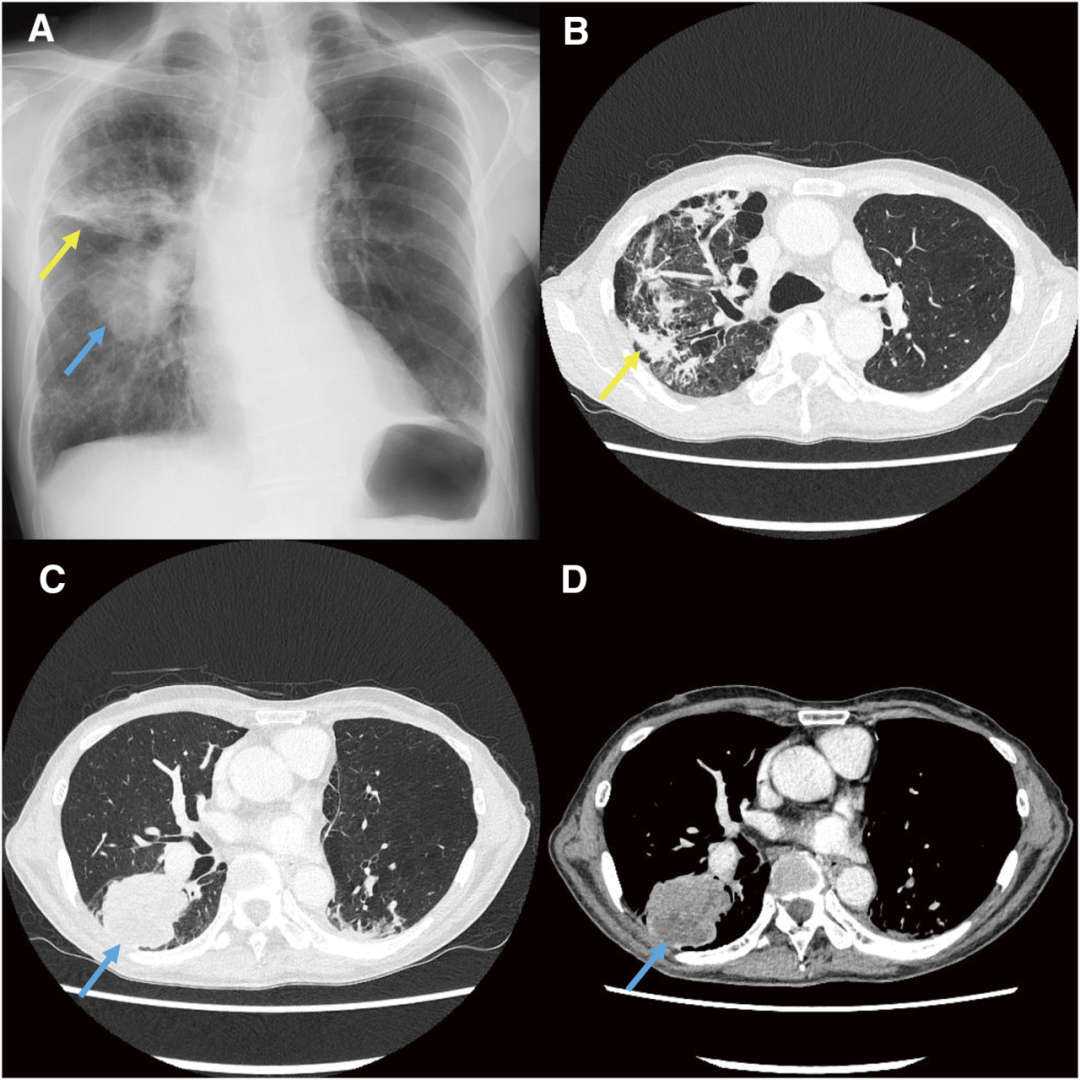

- 文献精读丨影像学随访是否已过时?ctDNA检测阳性如何预示低风险HR阳性乳腺癌患者晚期复发? 一项发表于Int J Mol Sci 期刊的病例研究介绍了1例在随访期进行ctDNA监测的低危激素受体阳性(HR+)乳腺癌患者的诊疗经过。本文系统整理了该病例的核心临床数据、治疗决策过程及ctDNA动态监测结果,以飨读者。……